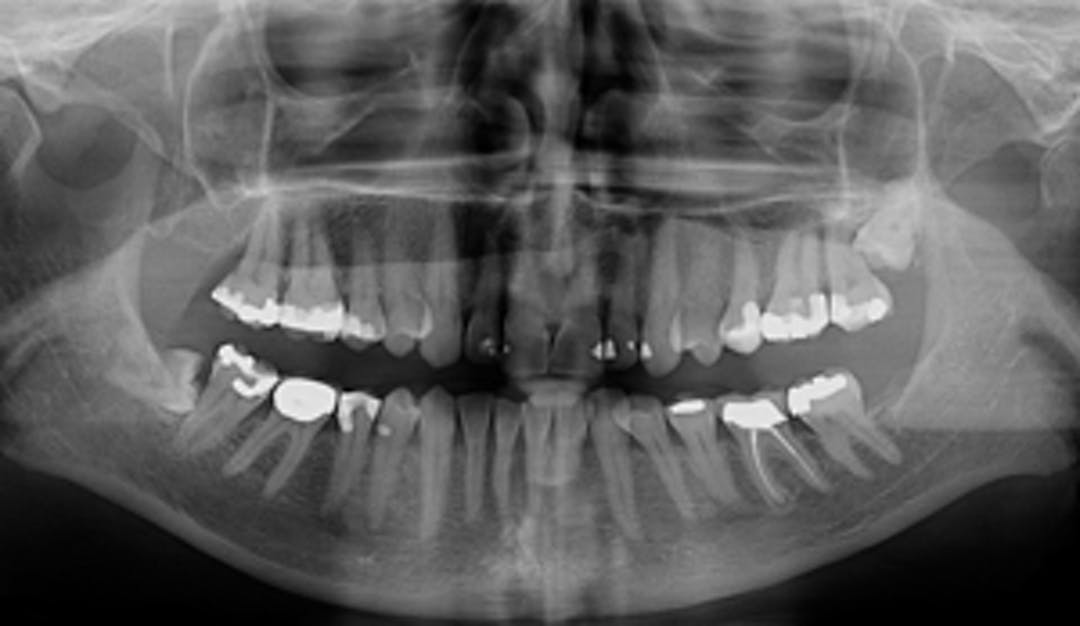

De fleste forbinder tannlegebesøket med en sjekk etter hull i tennene. En full undersøkelse kan avdekke mye annet...